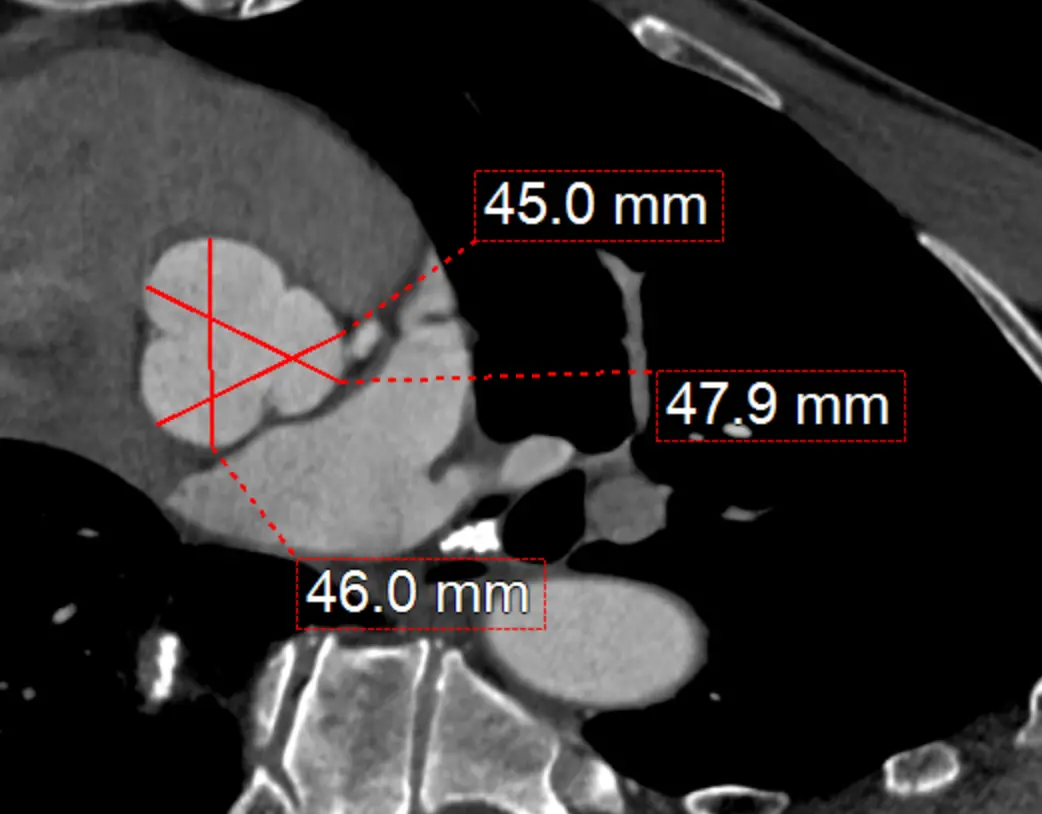

Measure at sinuses of Valsalva

- Measure aortic root diameter at the sinuses of Valsalva on CT

- Drag the lines until you see the widest section in the coronal and sagittal planes

- Now in your axial view (SAX), you will measure commissure to sinus.

- RCC measurement:

- Normally, this will be from the commissure between the LCC and NCC

- You will then drag up to the sinus of the RCC

- NCC measurement:

- LCC and RCC commissure â sinus of NCC

- LCC measurement:

- RCC and NCC commissure â sinus of LCC

- You can also measure from sinus-to-sinus